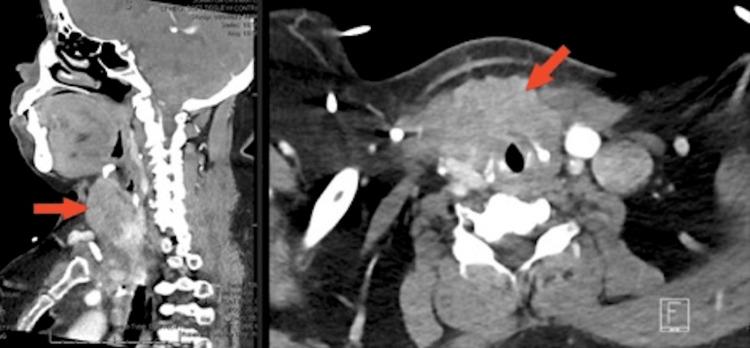

Recurrent Metastatic Colorectal Adenocarcinoma to the Thyroid Gland Presenting With Vocal Cord Paralysis and Inspiratory Stridor.

The most common sites for metastases of colorectal cancer include the liver, lungs, brain, and regional lymph nodes. However, a limited number of reported cases describe colon cancer metastasis to the thyroid gland. Metastatic colorectal adenocarcinoma to the thyroid gland is rare. The majority of these cases with colon cancer metastases to the thyroid gland are diagnosed years after initial treatment of colon cancer. The discovery is usually made after routine surveillance imaging, and often patients have minimal or absent symptoms. We report a case of a recurrence of metastatic colorectal adenocarcinoma to the thyroid gland presenting with vocal cord paralysis and inspiratory stridor.

结直肠癌最常见的转移部位包括肝脏、肺、脑和区域淋巴结。然而,仅有少数报道病例描述了结肠癌转移至甲状腺。甲状腺转移性结直肠腺癌较为罕见。这些结肠癌转移至甲状腺的病例大多在结肠癌初始治疗数年之后才得以诊断。通常是在常规监测成像后发现,而且患者往往症状轻微或无症状。我们报告一例甲状腺转移性结直肠腺癌复发的病例,该病例表现为声带麻痹和吸气性喘鸣。